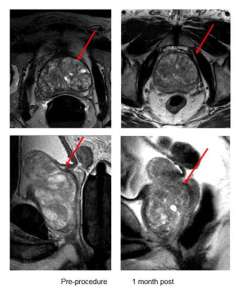

PAE Figure 2

Compared with surgical procedures such as open prostatectomy and TURP, PAE offers many benefits:

• Outpatient procedure

• Shorter recovery time

• Low risk of sexual side effects

• Low risk of urinary incontinence

• No indwelling Foley catheter

• No retrograde ejaculation

• Decreased pain and discomfort